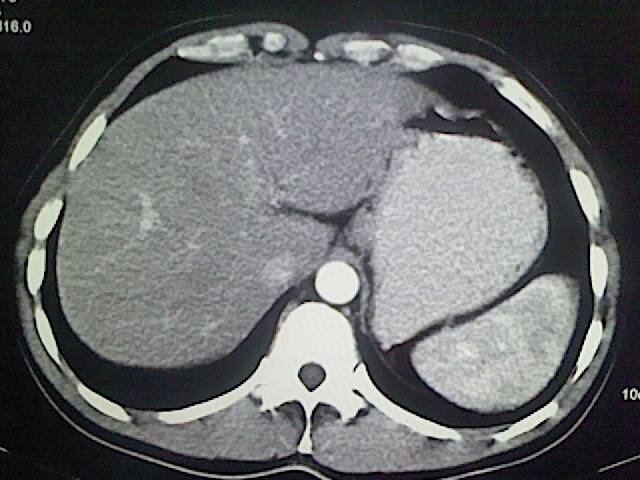

以下是引用卜一在2009-3-14 9:49:00的发言:[br]胆囊萎缩,胆囊壁不规则增厚,内部结构模糊,增强明显强化。另:肝左叶外侧段肝囊肿。支持:慢性胆囊炎!高度可疑:胆囊癌!

以下是引用余辉在2009-3-14 8:48:00的发言:[br]1)慢性胆囊炎。2)肝左叶外侧段肝囊肿。3)脂肪肝。[br]支持,胆囊萎缩,密度增高,不知b超具体有何提示,钙胆汁?结石?

以下是引用jiangjing在2009-3-14 10:18:00的发言:[br]1)慢性胆囊炎。2)肝左叶外侧段肝囊肿。3)脂肪肝。4.】建议行肝功能检查